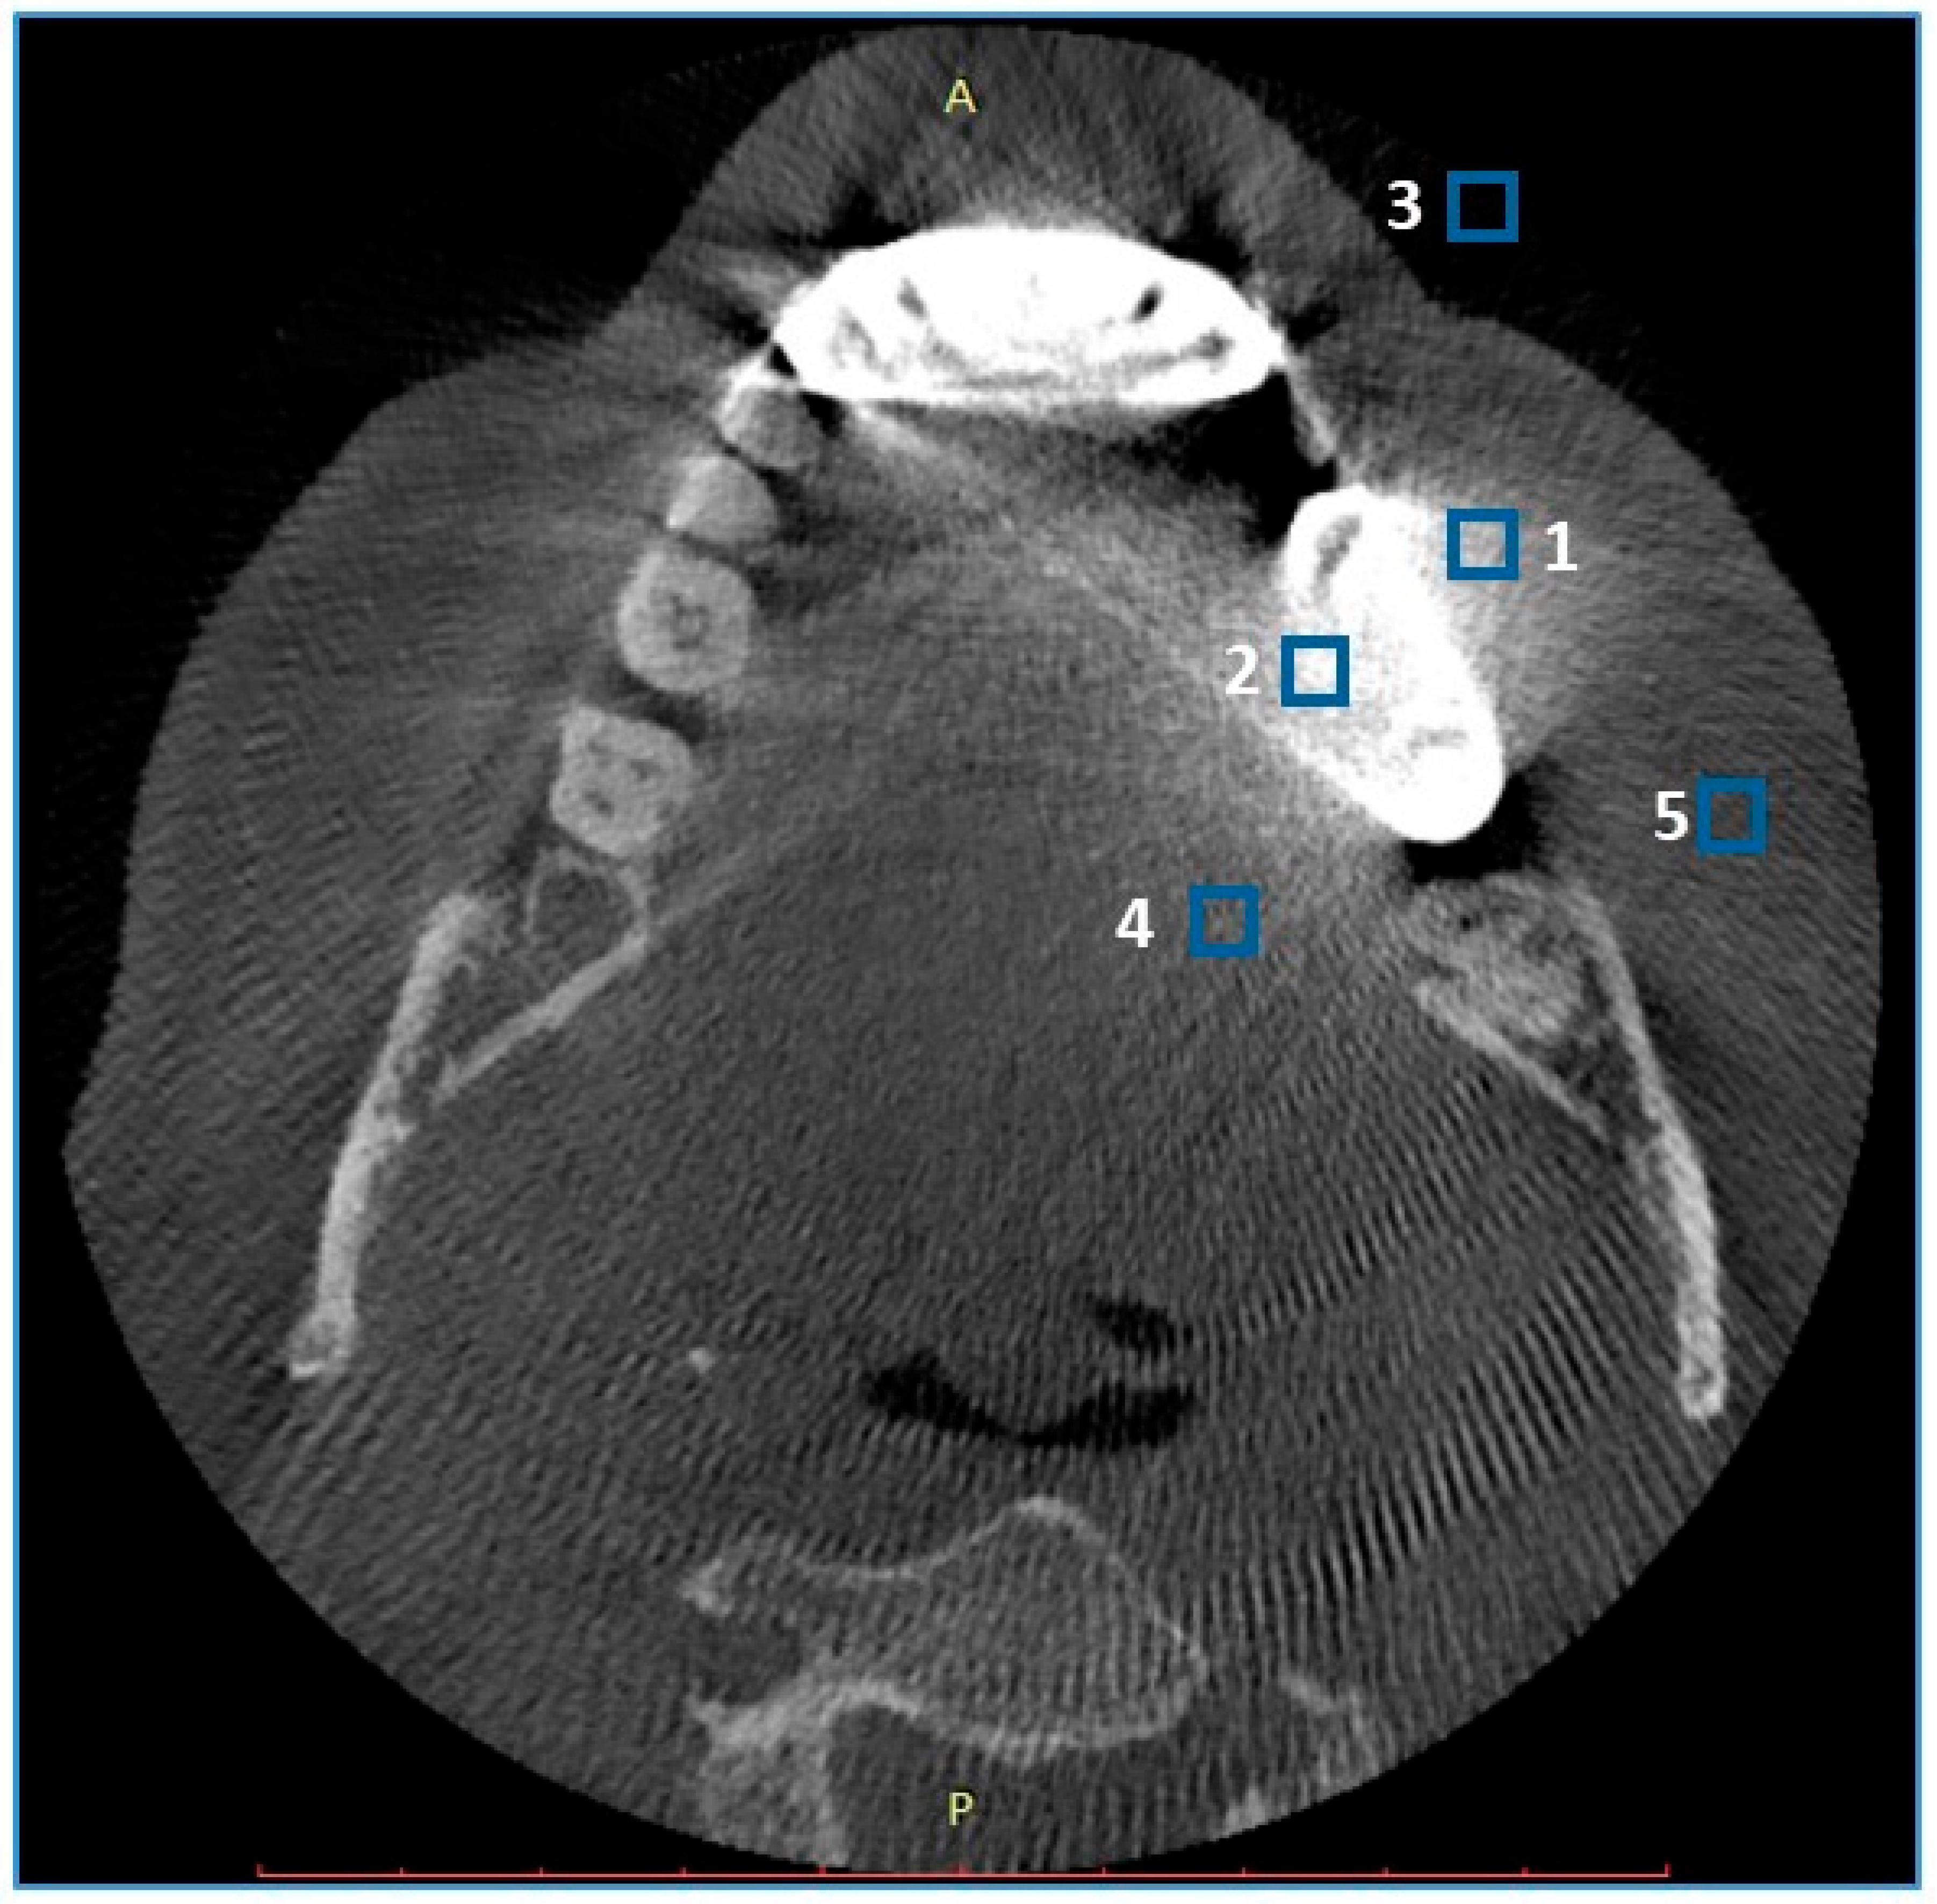

- -

- ROIs 1 and 2 in the near field (<10 mm) of the metal object, anterior and posterior to the object, preferable to homogenous bone tissue (spongious bone, dentine);

- ROI 3 in the air anterior to the skin;

- ROI 4 within the tongue musculature;

- ROI 5 within the subcutaneous adipose tissue of the cheek closest to the metal object.